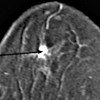

Внутритканевая маркировка образований молочной железы

Интерстициальная маркировка не пальпируемых молочных железистых образований. Диагностический метод позволяет уточнить расположение и границы опухолевого участка на ткани молочной железы. Процедура проводится перед органосохраняющей хирургией (секторальная резекция, лампэктомия) при фиброаденомах, доброкачественных опухолях, кальцинатах, раке молочной железы. Это позволяет радикально превзойти патологически измененные участки молочной железы, не удаляя лишние ткани. Маркировка выполняется под контролем цифровой, стереотаксической или ультразвуковой маммографии. В то же время специальное решение для маркировки вводится в отображаемый фокус с помощью иглы. После удаления патологический участок подвергается повторному рентгеновскому исследованию, чтобы убедиться, что резекция является точной.